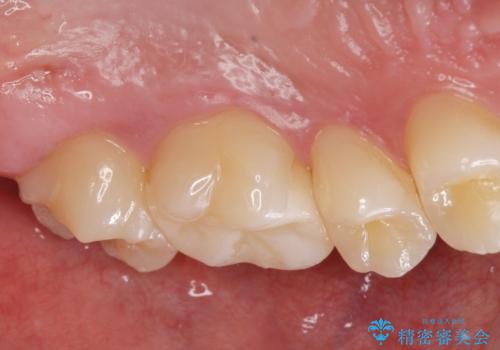

コンタクトカリエス治療。

- 歯と歯の間に虫歯(コンタクトカリエス)が見られたので拡大鏡下で取り除き、e-maxインレーで治療を行いました。

- e-maxインレー 7.7万費用は治療当時の料金となります